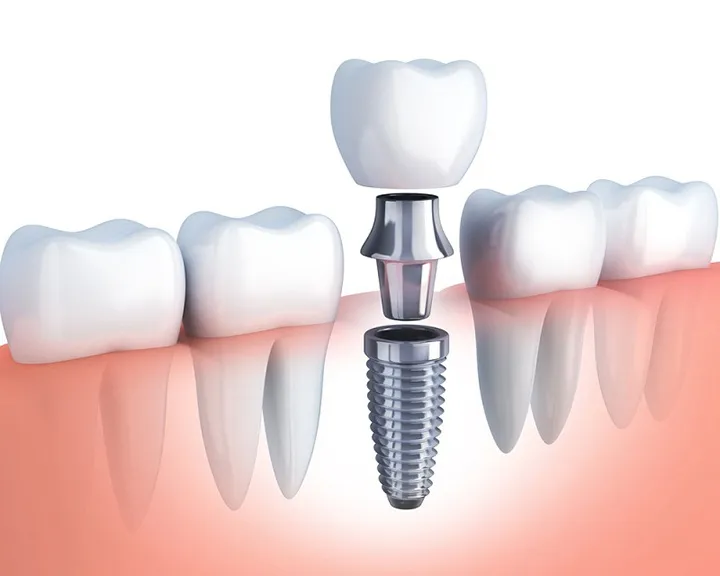

- Cầu răng trên implant: Đây là một kỹ thuật hiện đại hơn. Thay vì sử dụng răng thật làm trụ, chiếc cầu răng được nâng đỡ bởi các trụ implant đã được cấy ghép vào xương hàm. Phương pháp này đặc biệt hữu ích khi bệnh nhân bị mất nhiều răng liên tiếp hoặc không có răng thật khỏe mạnh để làm trụ.

Cả hai phương pháp này đều là giải pháp phục hình cố định. Tuy nhiên, chúng có những điểm khác biệt lớn về kỹ thuật và lợi ích lâu dài:

- Kỹ thuật và thời gian: Cấy ghép implant là một ca phẫu thuật, đòi hỏi thời gian lành thương và tích hợp trụ implant vào xương hàm, thường kéo dài vài tháng. Ngược lại, làm cầu răng sứ nhanh hơn, chỉ mất khoảng 2-3 buổi hẹn.

- Bảo tồn răng thật: Implant là phương pháp phục hình độc lập, không cần mài các răng bên cạnh, từ đó bảo tồn tối đa cấu trúc răng thật. Cầu răng sứ lại cần mài nhỏ các răng trụ, có thể ảnh hưởng đến chúng về lâu dài.

- Ngăn ngừa tiêu xương: Trụ implant được cấy trực tiếp vào xương hàm, kích thích xương hàm phát triển và ngăn ngừa tình trạng tiêu xương. Cầu răng, vì chỉ thay thế thân răng, không thể ngăn chặn quá trình này.